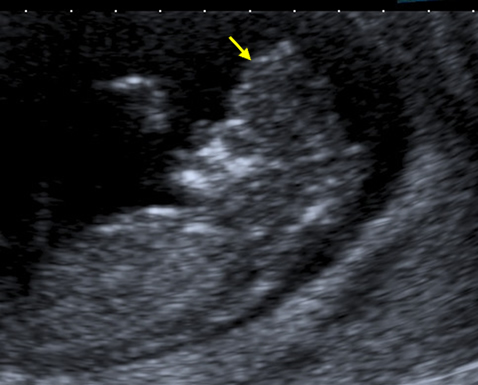

The anencephalic fetus demonstrates no clear frontal bone and often the facial bones may appear unusual also with the orbits appearing prominent – the so called 'frog-eyed appearance'. There may be some brain visible but this is variable. There is no bright skull vault covering the brain.

This image shows the facial view of an anencephalic fetus. Note the frog-eyed appearance. Also note that the skull vault is completely absent.